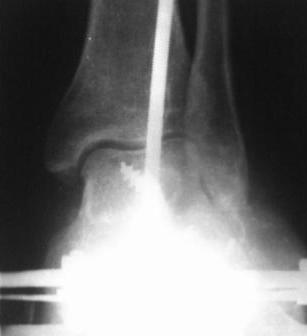

28.02.08г.  произведен  трехсуставной   артродез;  таранно-пяточного,

таранно-ладьевидного  и  пяточно-кубовидного  суставов,  с  клиновидной

остеотомией  пяточной  кости,  с  заполнением  синуса   костными

осколками.  Фиксация  таранно-пяточного  стягивающим  винтом,

таранно-ладьевидного  и  пяточно-кубовидного спицами,  варусная

деформация   стопы  устранена.  Для  наблюдения  за  состоянием  раны  и

стопы,  а  также  для   фиксации  и   поддержания  напряжения

произведен  к/остеосинтез  аппаратом  Илизарова.